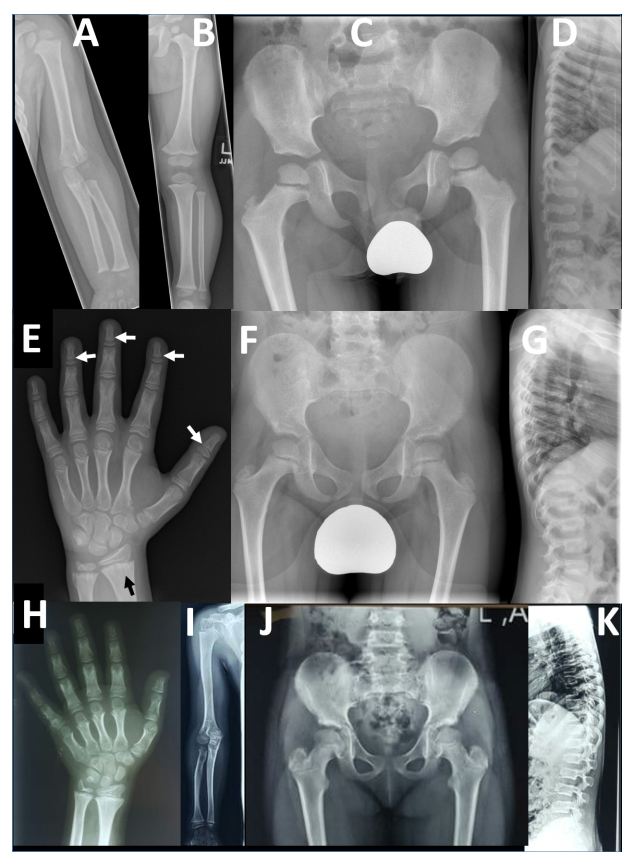

本研究提供了两个家系的详细表型信息,并与两个已发表的病例进行了比较。F2-V-3的放射学发现与之前描述的“先证者1”的放射学发现非常相似,这并不令人惊讶,因为这两个人都有相同的纯合子p.Arg569*。相反,PRKG2家族1有一致的放射学表型,不同于先前报道的AMDP和AMDM。

两个PRKG2变异家族的影像学表现

本文报告的三兄弟 (F1-IV-3、IV-6和IV-7)除了个别F1-IV-7有轻微的脚趾缩短外,没有肢端缩短 (Acromesomelic shortening)的证据。主要发现是颈椎病伴有椎体前突、股骨颈细长、干骺端不规则 (最明显的是桡骨和尺骨)和横纹(Striations)。其中一个儿童的远端指骨干骺端呈圆锥形,但是不显著。综上所述,家族1表现为以脊柱干骺端发育不良 (Spondylometaphyseal dysplasia)为特征的骨骼表型,而不是像AMDP和AMDM所预期的肢端发育不全。

F1- IV- 7的额外影像学表现